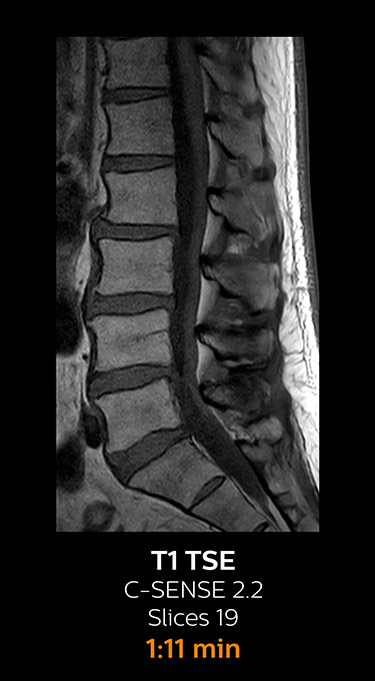

With Compressed SENSE, the scan time for the routine cervical spine examination at KNC was reduced from 13:11 to 9:52 minutes, which corresponds to 25% reduction.

MRI examination of the cervical spine with Compressed SENSE

Ingenia 3.0T CX

Scan time 9:52 min. (was 13:11 min. without Compressed SENSE)